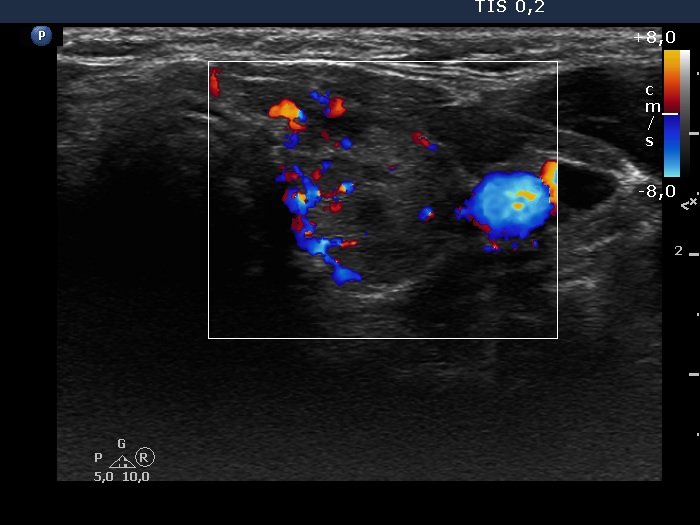

Consecutive patients with the final diagnosis of Hashimoto's thyroiditis - case 18 (1416) (ultrasonographic picture 7)

Left lobe, transverse scan, color Doppler mode. The vascularization is average.